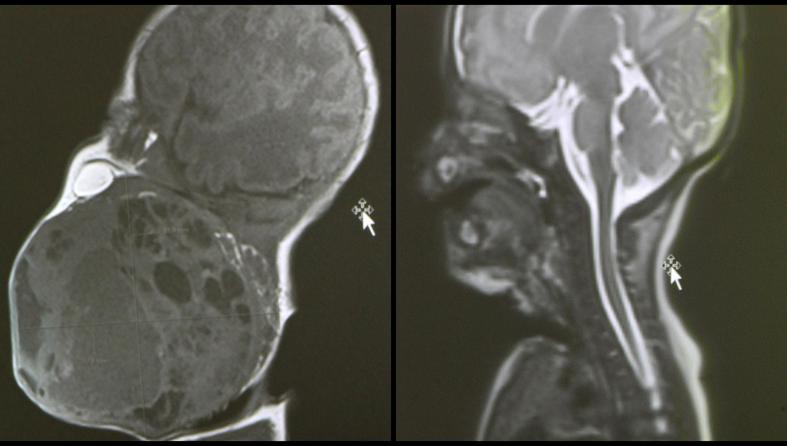

Prema nalazima magnetske rezonance prije poroda, tumor je bio gotovo veličine djetetove glave i zatvarao je dišne puteve. Dijete bi bilo životno ugroženo ako bi se rodilo normalnim putem, stoga je tim liječnika morao razraditi i biti spreman na nekoliko varijanti liječenja, a na kraju je profunkcionirala prva opcija.

"Tijekom carskog reza, kada je otvorena maternica, djetetova glava je izvađena, a ostatak tijela je bio u maternici pa je dijete bilo vezano za placentu i putem pupkovine dobivalo kisik. Pristupili smo glavi i pokušavali uspostaviti dišni put", objasnila je pročelnica Zavoda za neonatologiju i intenzivnu medicinu Ruža Grizelj. U sali je, kaže, bilo 20 ljudi.

"Kada smo bili sigurni da smo uspostavili umjetno disanje preko tubusa koji je stavljen u dušnik, tada smo rekli - idemo poroditi dijete. Dijete je izvađeno kompletno izvan maternice, podvezana je pupkovina i nakon što smo ga stabilizirali, istoga dana je učinjeno kompletno odstranjenje tumora s obzirom na to da smo nekoliko sati nakon samog poroda primijetili u intenzivnoj da se tumor povećava", rekla je Grizelj.

Voditelj Odjela za fonijatriju Ratko Prstačić pojasnio je da je patohistološka dijagnoza pokazala da se radi o teratomu, generalno dobroćudnom tumoru, ali s potencijalnom malignom opasnošću pa će dijete trebati onkološko praćenje, no druga terapija trenutačno nije potrebna.